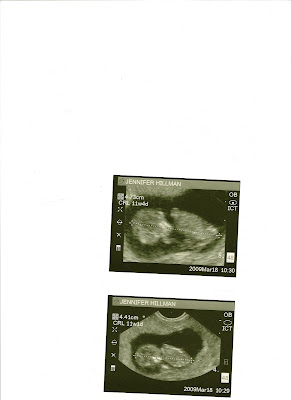

Not the best photos, I used my moms scanner so it was a little difficult getting it on here. But just wanted to share! So excited for a healthy little one

Re: PIP: U/S photos